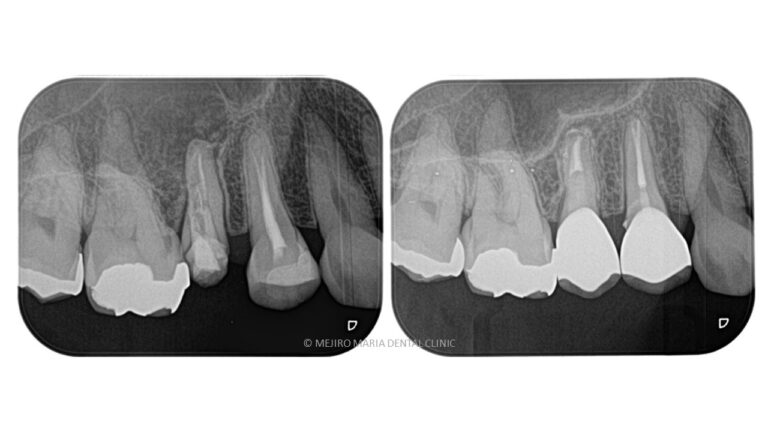

【再根管治療(感染根管治療)】

感染した歯髄や腐敗物、細菌を取り除く治療

再根管治療とは、過去に行った根管治療のやり直しを行う処置です。根尖性歯周炎の原因は根管内に潜む細菌感染ですので、根管内の細菌数を無菌的環境下で減少させ、密に封鎖することで予知性を高めることが可能です。

【歯根端切除術】

根管治療を行っても良くならない場合の外科的歯内療法

精密根管治療を施しても治癒に至らない場合、もしくは、被せ物を外すことが困難な場合(装着して間もない被せ物など)は歯根端切除術にて根尖性歯周炎を治癒に導くことが可能です。現代の歯根端切除術の成功率は90%以上で、破折していない歯であれば保存することが可能です。しかし、外科処置なのでリスクも当然あります。当院では精密根管治療初回カウンセリングにてご自身の歯の状態や診断から精密根管治療(歯内療法)後のリスクをお話した上で、治療介入を行うか患者様に決めていただいております。